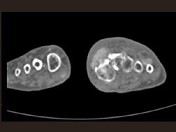

- 单项选择题男,55岁, 趾骨疼痛,皮肤红肿, 可触及结节,实验室检查高血尿酸, 结合图像,最可能的诊断是 ( )

C、痛风